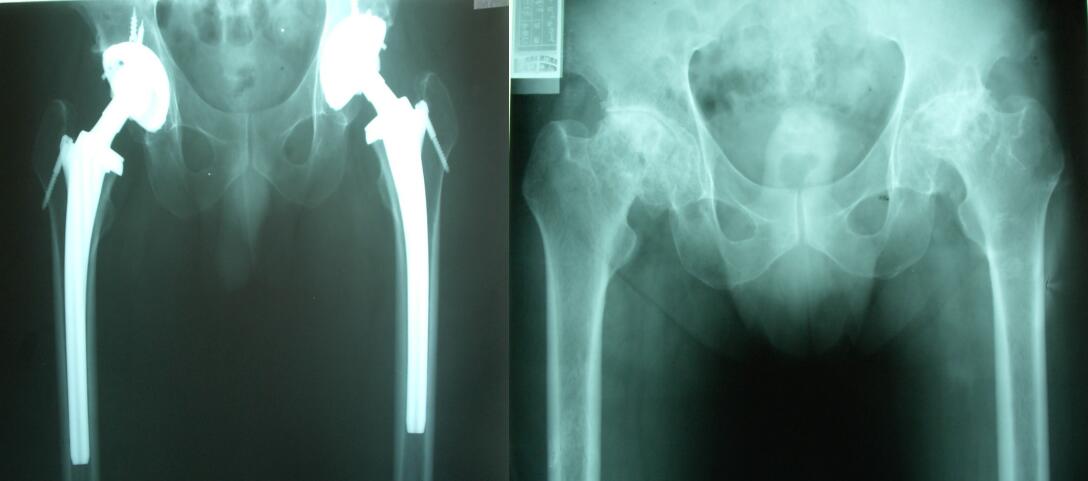

更多成功手術(shù)案例展示:

髖關(guān)節(jié)關(guān)節(jié)置換